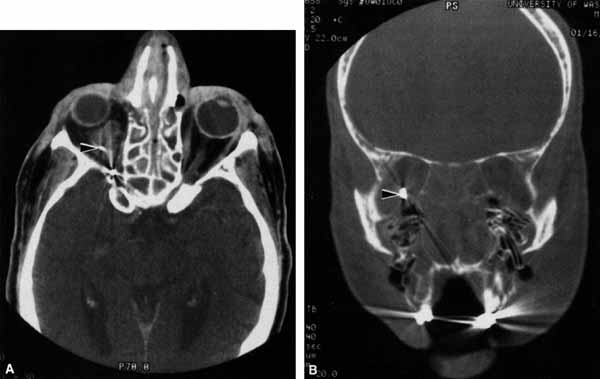

Anosmia caused by damage of cranial nerve I may be a helpful symptom of ethmoid or sphenoid sinus tumors invading the orbit (Fig. 20).44 Olfactory groove meningiomas and esthesioneuroblastomas may also present with anosmia prior to developing vision loss.45 Trauma that involves the orbit and is associated with anosmia should be considered a basilar skull fracture with potential for cerebrospinal fluid leak until proven otherwise (Fig. 21).

Fig. 20 A 13-year-old child presented with a 2-week history of sinusitis and anosmia. Her visual acuity decreased to to 20/400 1 day prior to admission. Computed tomography shows a large ethmoid tumor extending through the cribriform plate and optic canal. A rhabdomyosarcoma was diagnosed by biopsy.

Fig. 21 A 21-year-old man sustained a skull fracture from a motor vehicle accident 2 months prior to this examination. The patient describes anosmia since the accident. Computed tomography discloses a large medial wall orbital fracture extending through the cribriform plate (arrow). Orbital reconstruction was performed through a frontal craniotomy where dura was found incarcerated within the fracture. The orbital fracture was repaired by cranial bone grafting.